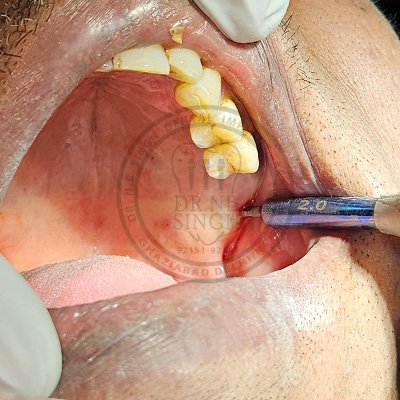

Case – 11 Baleram